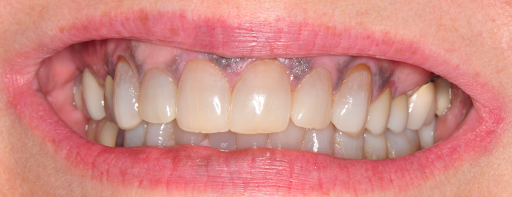

Close-up of a person's upper and lower teeth, showing gingival recession defects on #6 and #11 covered by gum grafts.

After